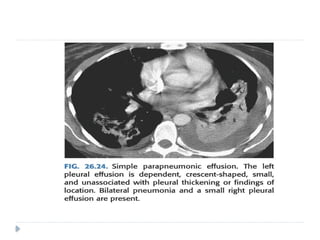

 Parapneumonic effusions are most common and are

usually secondary to pulmonary infections.